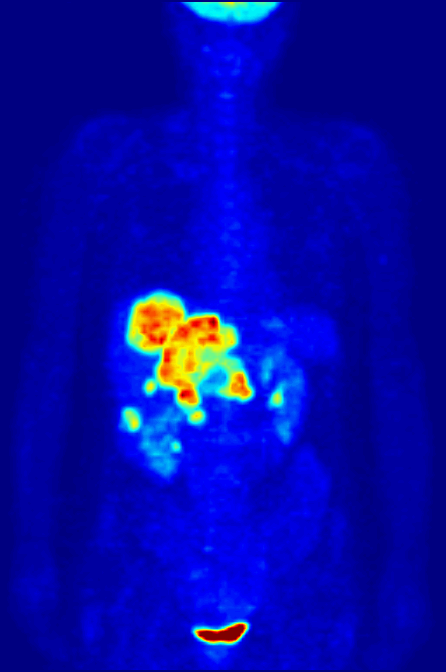

Pozytonowa tomografia emisyjna, PET

PET-MIPS-anim.gifPrzykład techniki z medycyny nuklearnej, czyli korzystamy z promieniotwórczych izotopów. Na animacji maksimum absorpcji fludeoksyglukozy, godzinę po podaniu.

Zasada działania: wykorzystujemy izotopy dokonujące rozpadu β+, czyli z emisją pozytonu (antycząstki elektronu). Taki pozyton po trafieniu w elektron powoduje ich anihilację, czyli zamianę na dwa fotony o energii 511keV (zgodnie z zasadą zachowania energii i słynnym E=mc²), lecące prawie dokładnie w przeciwnych kierunkach. Czemu prawie? Bo musimy uwzględnić zasadę zachowania pędu. Detektory są ustawione tak, żeby wychwytywać tylko takie fotony, i dodatkowo “parować je” wg czasu ich przybycia, aby określić gdzie dokładnie powstały. Nie jest to dokładnie miejsce rozpadu beta plus, ale dokładność jest rzędu milimetrów.

Co widzimy: to gdzie odłożył nam się nasz izotop. Np. gdy zastosujemy fludeoksyglukozę (pochodną glukozy, zachowująca się ciele niemal identycznie) z izotopem ¹⁸F, to będziemy mieli informację gdzie najsilniej metabolizowana jest glukoza. A silny metabolizm glukozy może wskazywać na rosnącego, aktywnego guza. Można znakować też inne związki i sprawdzać jak się odkładają w organizmie, i na tej podstawie zdiagnozować choroby Parkinsona, Huntingtona, czy ocenić efekt radioterapii.

Ograniczenia i zagrożenia: promieniowanie - o ile przy RTG i CT naświetlany człowieka przez chwilę, tak przy PET wprowadźmy substancje radioaktywne do jego ciała, i pacjent sam jest zagrożeniem dla ludzi wokoło niego. Przez kilka dni powinien unikać tłumów (np. komunikacji miejskiej) i dzieci, mocz i kał powinien izolować i oddawać do zakładu medycyny nuklearnej, póki się nie oczyści z izotopu. No i koszt - wytworzenie odpowiedniego związku do wprowadzenia swoje kosztuje, i nie można go za długo przechowywać, bo izotop się rozpadnie.

Ciekawostki: aparaty PET rzadko spotyka się jako samodzielne urządzenia - częściej jako hybrydy z CT lub MRI, co pozwala przeprowadzać te badanie równocześnie i nakładać obrazy jeden na drugi.